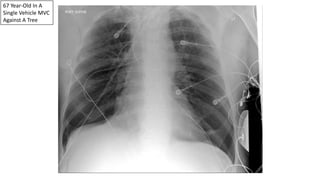

67 Year-Old In A

Single Vehicle MVC

Against A Tree

Wide

Mediastinum

Loss Of The

Aortopulmonary

Window

Traumatic

Pseudoaneurysm

Successfully Deployed

Endovascular Stent

Graft